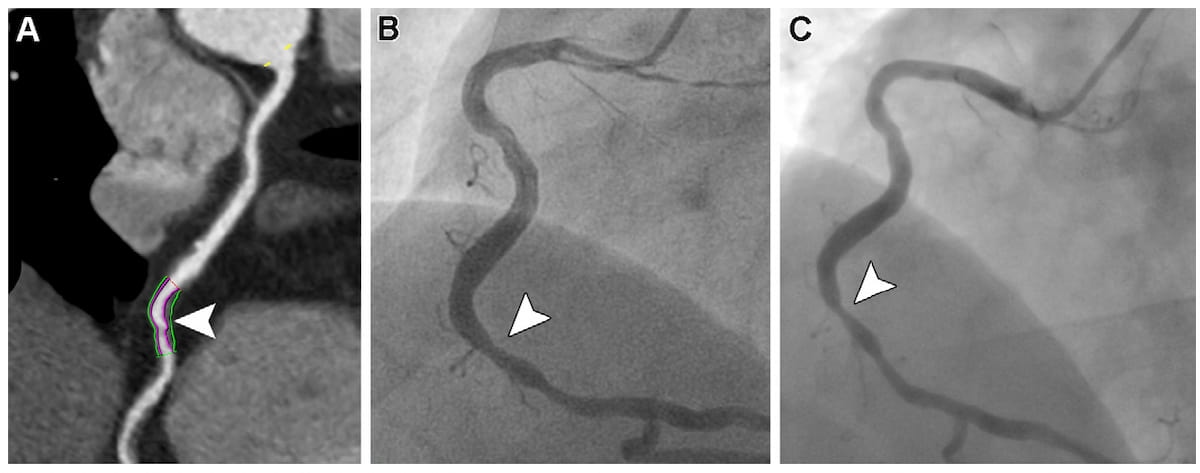

Abnormal findings on coronary computed tomography angiography-derived fractional flow reserve (CCTA-FFR) are associated with 3.2-fold higher risks of all-cause death or spontaneous myocardial infarction (MI) in patients with new-onset stable angina pectoris and coronary stenosis, according to newly published research.